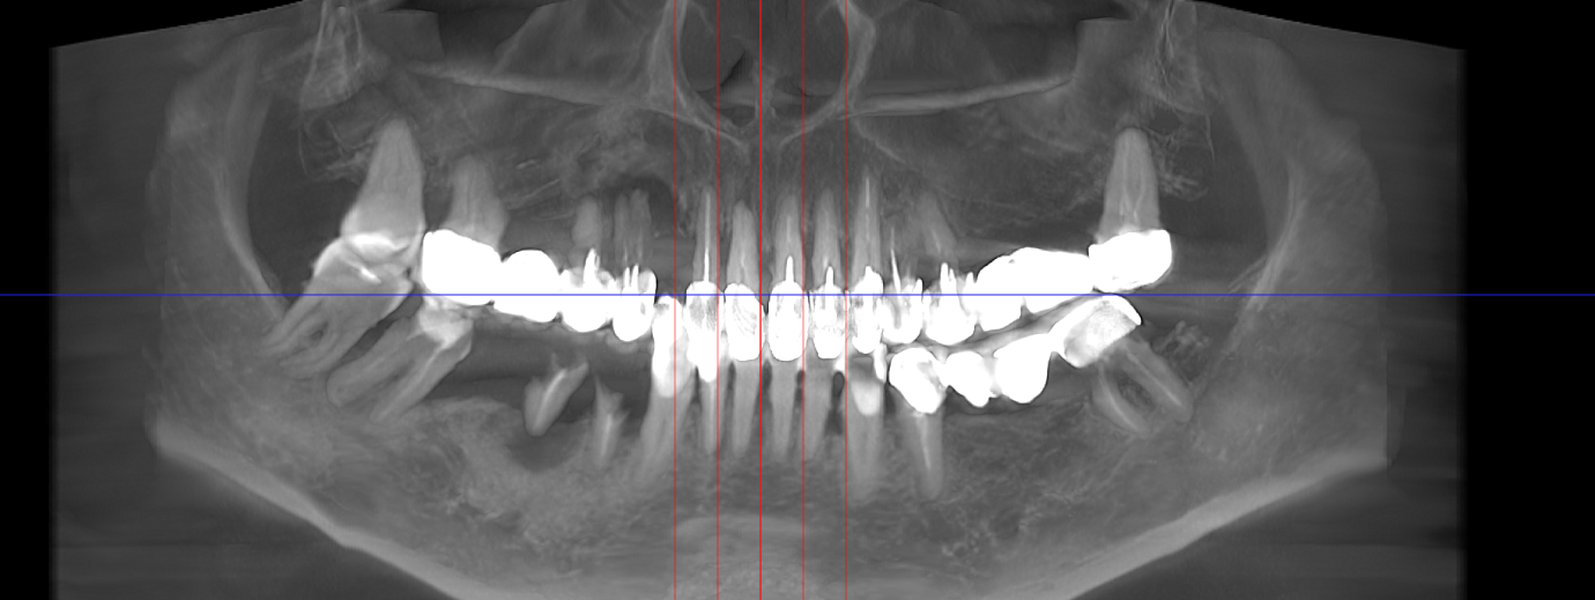

- Investigație imagistică completă, ideal CBCT (computer tomografie);